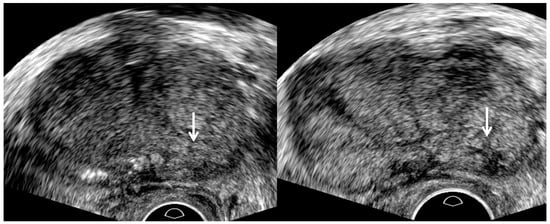

3. TRUS Imaging Features

| TRUS Parameters | Old TRUS Techniques | New TRUS Techniques |

| US sequence | Harmonic imaging | Fundamental imaging |

| US artifacts | Rare | Frequent |

| Dynamic range | High | Low |

| Image resolution | High | Low |

| Tissue contrast | Low | High |